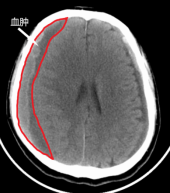

慢性硬膜下血肿是颅内硬膜下腔(硬脑膜与蛛网膜之间的腔隙)的陈旧性血肿,多见于老年人,常在头部创伤3周以后形成。

慢性硬膜下血肿多由于头部创伤导致,创伤可为头部摔伤,或者轻微的头部碰撞,甚至不经意的剧烈头部摇晃,这些原因都会导致脑表面的桥静脉撕裂,导致硬膜下出血。这些颅内出血由于炎症的原因,难以自行吸收,并且会持续增多,最终大概在创伤3周以后演化为典型的慢性硬膜下血肿。

如老人有头部外伤史,并且出现了以上临床表现,行头部CT检查即可作出诊断。